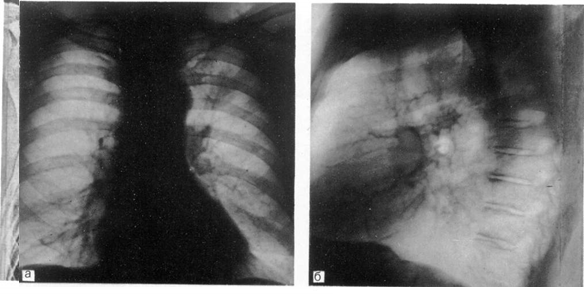

Рис. 3. Рак верхней доли левого легкого.

а — прямая рентгенограмма: б — боковая рентгенограмма.

Последующее рентгенографическое обследование должно углублять и расширять представления о характере изменений в легких и грудной полости. Эти исследования проводят в прямой (переднезадней) и боковой проекциях, дополняя их при необходимости снимками в косых проекциях и прицельными рентгенограммами (рис. 1). Важным достоинством рентгенографии являются объективность и достоверность полученных результатов, возможность сопоставления с данными ранее проведенных рентгенографических обследований, т. е. возможность динамического наблюдения. Последнее нередко является одним из важнейших факторов дл я установления правильного диагноза.

Рентгенографическое обследование в двух проекциях позволяет с наибольшей точностью определить локализацию и распространенность поражения легких, изменения в средостении, состояние междолевых щелей, оценка и сопоставление степени прозрачности участков легкого в различных его отделах, мельчайшие очаговые тени, что особенно ценно при проведении дифференциального диагноза между туберкулезом легких, саркоидозом, пневмокониозом и другими заболеваниями, дающими исходные рентгенологические изменения.